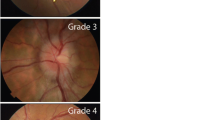

A comprehensive dissertation about the clinical aspects of IH is outside the scope of this chapter. However, in order to define IH and ICS operatively, we need to introduce the concept of ICP monitoring, which is often applied in patients with ABI. Whichever the technology adopted (e.g., intraparenchymal probe, intraventricular catheter), the measure of ICP allows the clinician to react adequately if the patient reaches a critical threshold level, which defines IH [3]. Historically, the most frequently adopted ICP cutoff to define IH has been 20 mmHg, which is derived from the seminal Lundberg study [4]. More recent research tend to confirm this cutoff, showing that an ICP above 20 mmHg correlates with mortality and poor outcomes [5, 6]. However, the latest Guidelines for the Management of Severe Traumatic Brain Injury recommend treating ICP values above 22 mmHg [7], thus implying that lower values should not be considered as IH and suggesting that below that level the patient should not be at risk of ICS. This new threshold fired the debate since many experts do not agree with such strict limits and recommend that the diagnosis of IH (and of ICS) be based not only on a mere number but on a complete clinical picture of the patient [3, 8, 9]. IH should be considered in terms of insult severity and duration possibly with the aid of multimodal neuromonitoring [3, 8, 9].